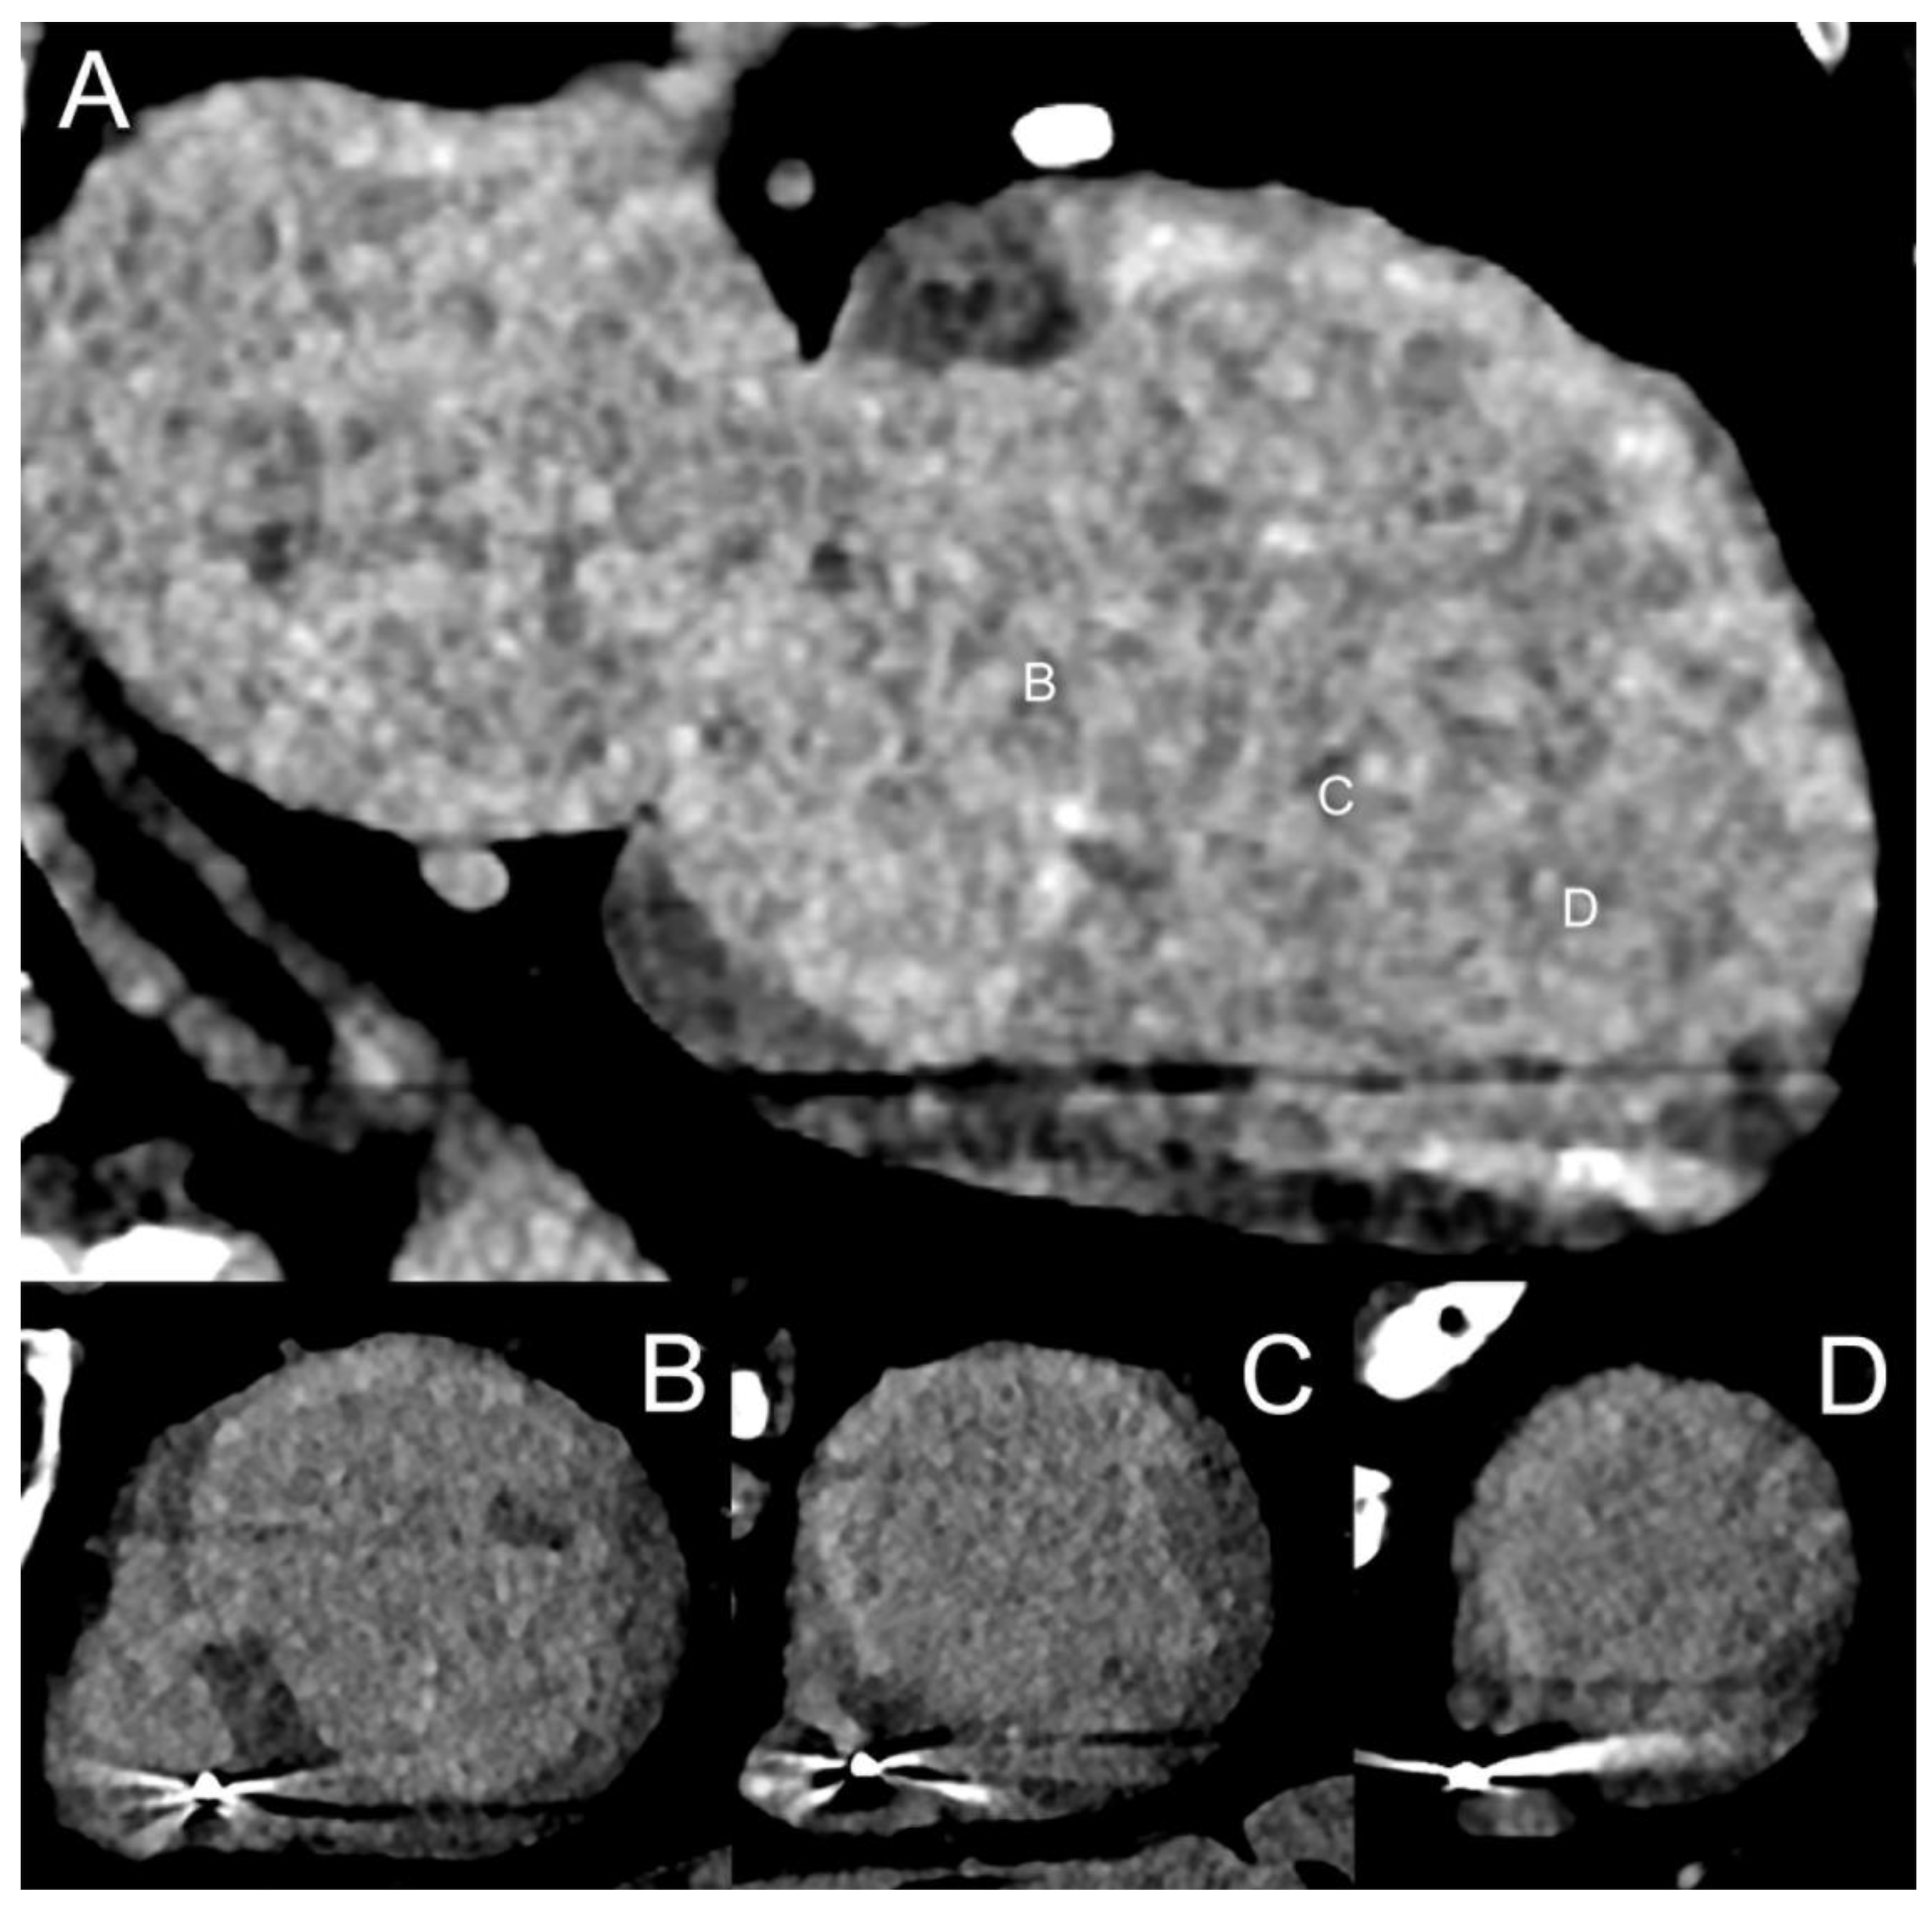

3.5. Radiomics